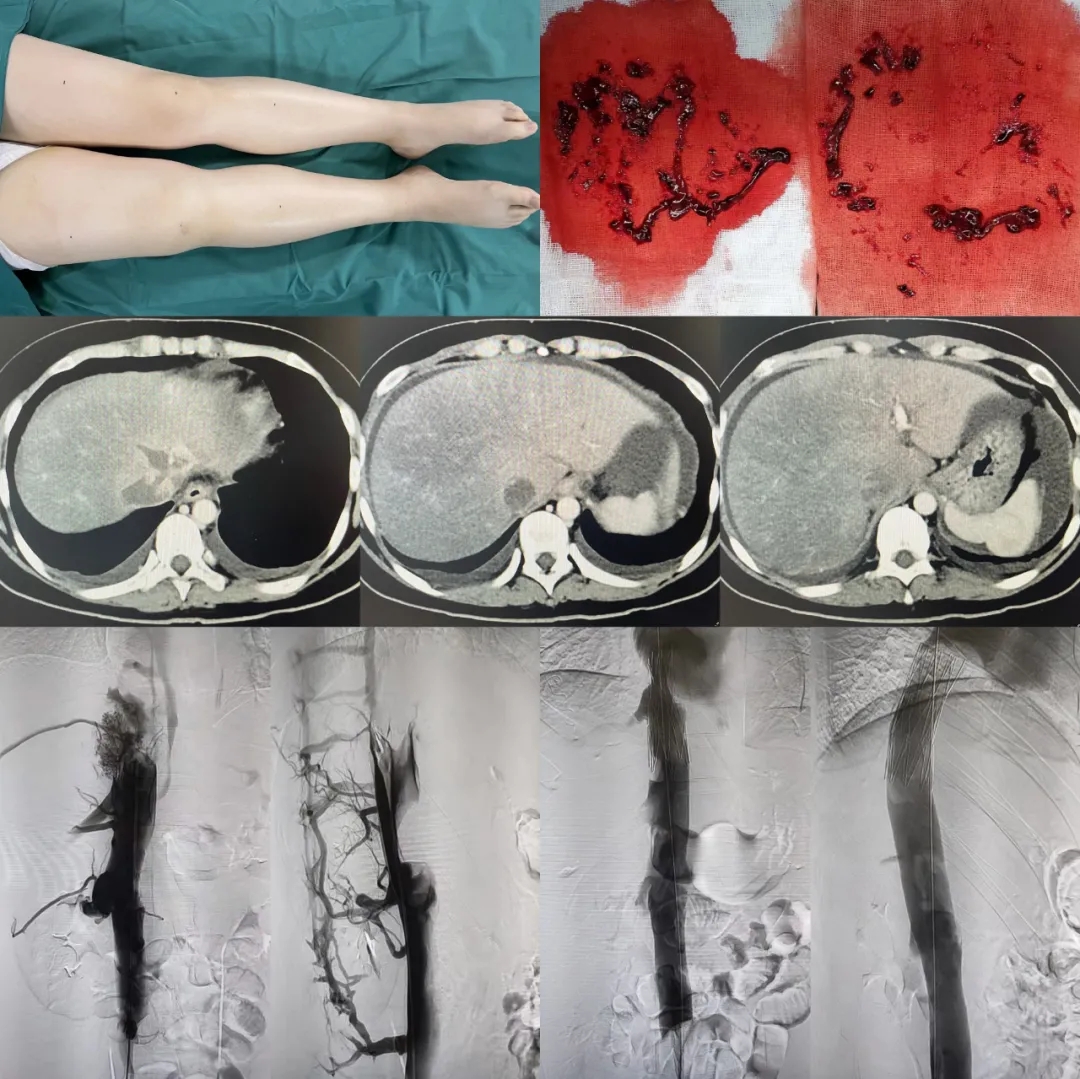

5天時(shí)間過去了,小李的癥狀非但沒有減輕,胸悶氣短也越發(fā)加重,并且出現(xiàn)了大量腹腔積液以及嚴(yán)重的雙下肢水腫。下腔靜脈的血管成像檢查后,報(bào)告顯示:下腔靜脈血栓形成,考慮腫瘤性病變!這個(gè)消息對(duì)于小李和她的的家人無異于晴天霹靂,她是家里的獨(dú)生女,經(jīng)過多年的寒窗苦讀,才參加工作,剛開始的美好生活卻要被突如其來的病魔殘忍的畫上句號(hào)。小李的家人無論如何也不能接受。父親多方詢問求醫(yī),希望能夠找到一線生機(jī),輾轉(zhuǎn)至北京知名醫(yī)院,專家告訴她的家人可以前往西安國際醫(yī)學(xué)中心醫(yī)院,尋求韓國宏教授的幫助,或許有辦法。

5月2日,家人懷揣著一線希望找到了西安國際醫(yī)學(xué)中心醫(yī)院消化病醫(yī)院執(zhí)行院長(zhǎng)韓國宏。他得知小李的病情后,仔細(xì)的詢問小李的病史并查看影像學(xué)資料。之后,韓國宏院長(zhǎng)親自陪她在超聲下查看血栓的情況,排除惡性病變,考慮為布加綜合征,并決定馬上手術(shù)。

什么是布加綜合征?布加綜合征是一種較為少見的疾病,是由于肝靜脈或肝段下腔靜脈梗阻,血液回流出現(xiàn)障礙而導(dǎo)致的,表現(xiàn)的癥狀通常是腹水、雙下肢水腫、肝脾腫大、腹壁靜脈曲張、下肢潰瘍、消化道出血等。布加綜合征患者若進(jìn)一步發(fā)展,就會(huì)有肝衰竭風(fēng)險(xiǎn),甚至危及生命。小李正是因?yàn)橄虑混o脈急性血栓形成才會(huì)出現(xiàn)上述的癥狀,并且她的下腔靜脈血栓進(jìn)展已經(jīng)非常嚴(yán)重,不僅現(xiàn)有的癥狀得不到緩解,還影響了肝臟血液的回流造成嚴(yán)重的肝淤血,代表肝細(xì)胞破壞的轉(zhuǎn)氨酶在持續(xù)升高。

5月4日,在韓國宏院長(zhǎng)的帶領(lǐng)下,消化介入科醫(yī)、技、護(hù)團(tuán)隊(duì)急診行下腔靜脈的開通治療,術(shù)中抽出了大量的血栓組織,并對(duì)近心端的血栓部位進(jìn)行了開通治療,術(shù)后小李的惡心、嘔吐癥狀有所減輕。5月5日,韓國宏院長(zhǎng)率領(lǐng)團(tuán)隊(duì)再次為小李進(jìn)行下腔靜脈支架植入術(shù),術(shù)中造影可以看到血流終于通暢的回流到了心臟。術(shù)后小李的癥狀明顯緩解,下肢的水腫也逐漸的減輕。目前已經(jīng)恢復(fù)進(jìn)食和活動(dòng)。